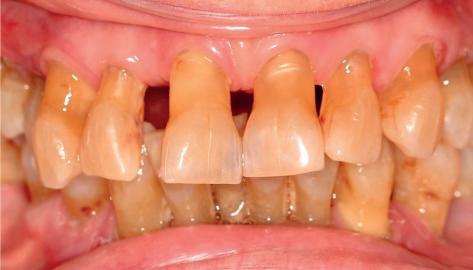

CASE STUDY

Guided implant approach for reproducible results, page 28